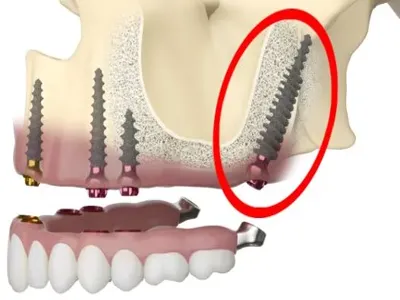

Elevate your dental care journey with our membership program, specifically designed for patients seeking teeth implants. As a member, you’ll benefit from reduced pricing on implant procedures, priority scheduling for consultations and treatments, and continuous follow-up care to ensure the best outcomes. Join today to access top-tier dental implant services and enhance your smile with confidence.